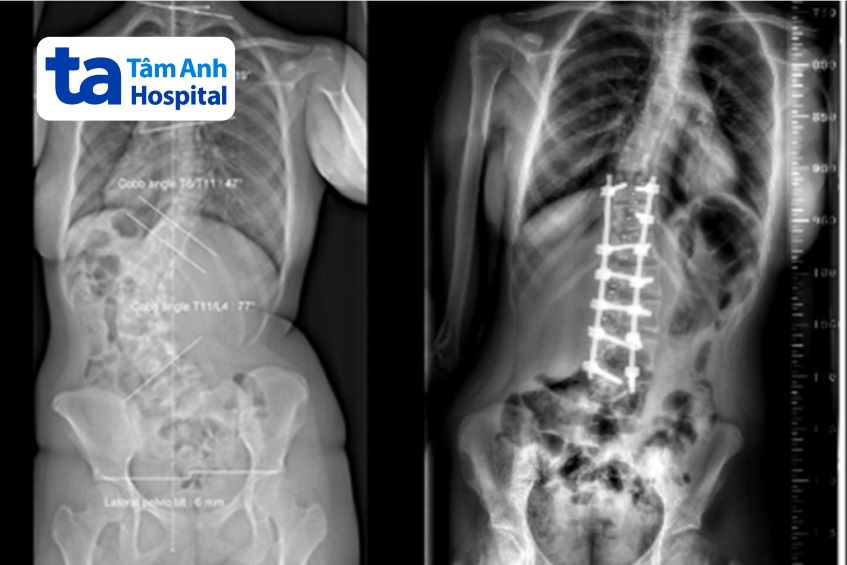

Kết quả chụp X-quang tại Bệnh viện Đa khoa Tâm Anh cho thấy cột sống của An có hai vùng biến dạng, vùng ngực vẹo sang phải 47 độ và vùng thắt lưng vẹo sang trái 77 độ, thắt lưng xoay nhiều. Tình trạng khiến người bệnh bị lệch vai, lưng biến dạng có thể nhận ra bằng mắt thường và đau nhiều khi ngồi.

An được phẫu thuật nắn chỉnh cột sống lối sau. Phương pháp này phù hợp với những trường hợp vẹo nặng và phức tạp, giúp chống xoay, kéo dài và ổn định cột sống theo cả ba chiều không gian. Bác sĩ tiến hành mở một đường dài sau lưng, bộc lộ các vùng cột sống bị biến dạng cong vẹo.

Sau đó đặt các vít chân cung vào các đốt sống bị biến dạng xoay ở vùng cong vẹo, nắn chỉnh các đốt sống và nối chúng lại với nhau bằng thanh kim loại với mục đích cố định, giữ cột sống vùng vẹo sau khi nắn chỉnh.

Theo bác sĩ Dũng, ca phẫu thuật hướng tới mục tiêu nắn chỉnh cân bằng cột sống trở lại, từ đó giúp người bệnh cải thiện dáng đi, vùng vẹo và bảo tồn tầm vận động thắt lưng. Riêng phần cong vẹo cột sống vùng ngực còn mềm dẻo nên An được điều trị bảo tồn bằng tập vật lý trị liệu, hướng dẫn bơi đúng cách. Hậu phẫu, An phục hồi tốt và được xuất viện sau 7 ngày phẫu thuật. Tiên lượng sau 3 tháng, người bệnh sinh hoạt bình thường. “Sau mổ, lưng em đã thẳng hơn, không xiêu vẹo như trước đây, em không còn cảm thấy tự ti nữa”, An vui vẻ cho biết.